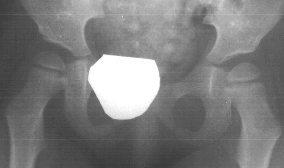

adductor longus and gracilis release were performed. At 4y.+ 2m., she

could ambulate with a walker. Hip abduction was 60 degrees bilaterally.

Popliteal angle was 30 degrees bilaterally, x-ray showed normal hips.